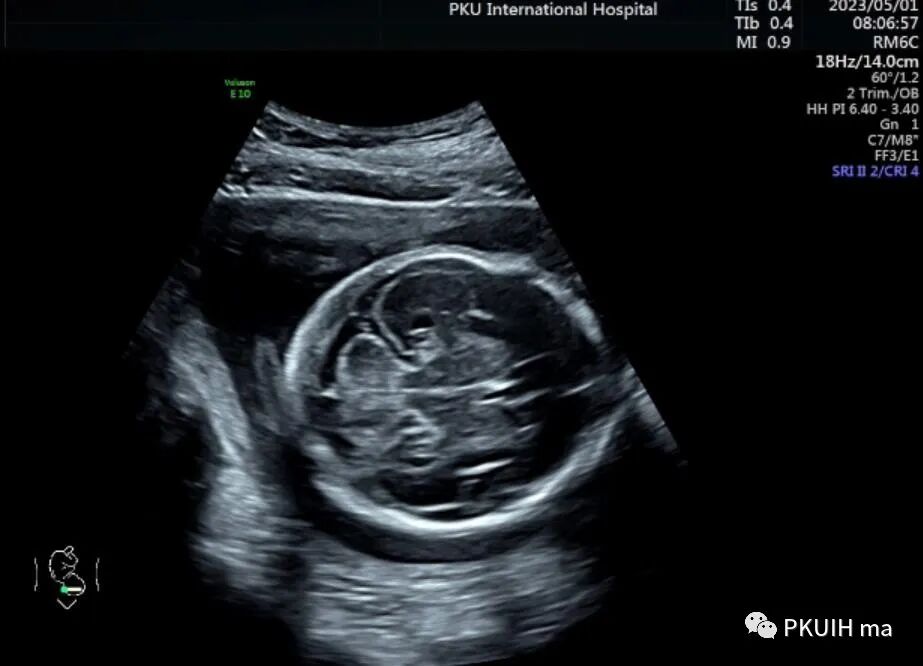

胎儿心脏大部分位于右侧,心尖指向右前方,左房位于脊柱前方,右室位于胸骨后方,右室心尖部可见调节束,心室–大动脉连接关系正常,整个心脏呈镜面右位心。